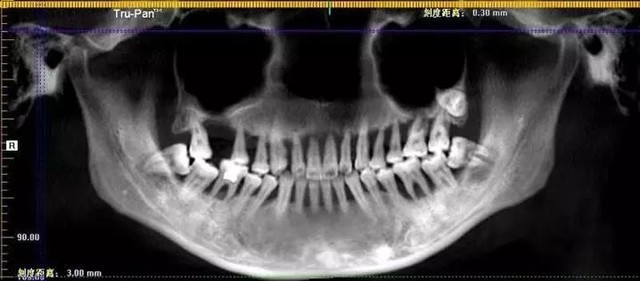

一个28岁的姑娘,张嘴却是一口如82岁老太太般的牙齿,大部分因不同程度的松动而丧失咀嚼功能。牙齿这样结果的罪魁祸首就是牙周病!比如常见的刷牙时出血、牙龈红肿等,若不及时治疗可蔓延至全口牙,导致严重的牙周病。

这位28岁的姑娘其实6年前就出现了两颗牙松动,看过牙医后她只是使用了消炎药,并未当回事,直到6年后门牙脱落再就诊,牙龈和牙槽骨严重萎缩,牙根都暴露在外面,给后续的种牙也增添了不少的难度。

主要临床表现是牙龈炎症、出血、牙周袋形成、牙槽骨吸收、牙槽骨高度降低、牙齿松动、移位、咀嚼无力,严重者牙齿可自行脱落或者导致牙齿的拔除。

3.慢性炎症其反复发作渐进性发展,临床上主要以牙槽骨吸收牙齿松动为症状,渐而引起咬合创伤使牙齿移位,最后造成牙齿的缺失,剩余牙支持力差,造成修复治疗困难。